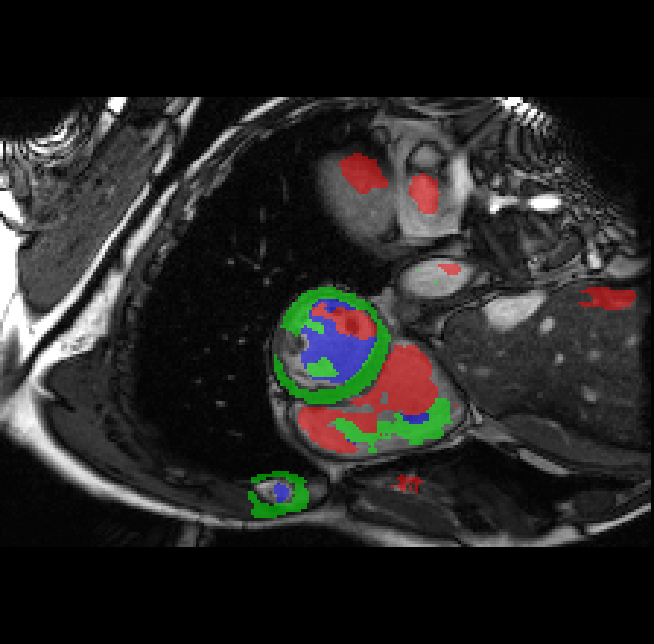

First, an edge detector is applied to the input image and a full edge map FF is obtained. However, the edge map contains many edges unrelated to a given target object’s boundary (Fig. 2(c)). To distinguish the boundary edges from the noisy edges, we design an iterative scheme. Fig. 2 visualizes the procedure for a single iteration. In the first iteration, we initialize a counting map with same size as the input image and use a square kernel with a size of k1k_{1} to dilate the scribbles (Fig. 2(a) and (b)). The counting map and dilated scribbles for class cc are denoted as U1,cU_{1,c} and S1,cS_{1,c}, respectively. Similar notations, Ui,cU_{i,c} and Si,cS_{i,c} are used for the ii-th iteration. The initial boundary edges are identified through E1,c=S1,cU1,cFE_{1,c}=S_{1,c}\wedge U_{1,c}\wedge F, as seen in Fig. 2(c) and  2(d), where \wedge is the logical AND operator. In the second iteration, a larger square kernel with a size of k2k_{2} is used to dilate the scribbles and obtain S2,cS_{2,c}. The counting map value U2,c(x,y)=1U_{2,c}(x,y)=1 if the total value of the E1,cE_{1,c} patch centered at (x,y)(x,y) with a size of k2×k2k_{2}\times k_{2} is less than ncn_{c}, which is a predefined threshold; otherwise U2,c(x,y)=0U_{2,c}(x,y)=0. This threshold sets an upper limit on how many edge pixels can be added to the object boundary map at each iteration, reducing the risk of mistaking noisy edge-pixels with true boundary pixels as kernel sizes grow larger. The boundary edges identified in the second iteration are E2,c=S2,cU2,cFE_{2,c}=S_{2,c}\wedge U_{2,c}\wedge F. This process is repeated jj times with increasing kernel sizes. Fig 2(e) shows an example of the final object boundaries.

Refer to caption

Figure 2: Visualization of one iteration in the boundary estimation algorithm. (a) SiS_{i} shows the dilated scribble and (b) UiU_{i} the counting map for the boundary map EiE_{i} at the current step ii. Blue regions in (a) and (b) represent pixels, for which the operations in SiS_{i} and UiU_{i} hold true respectively. SS and UU are logically combined with the edge map FF to extract edge pixels, which are added to update the boundary map to Ei+1E_{i+1}. The process is repeated jj times for all kernel sizes and for every class to generate the final boundary map EE, as shown in (e).